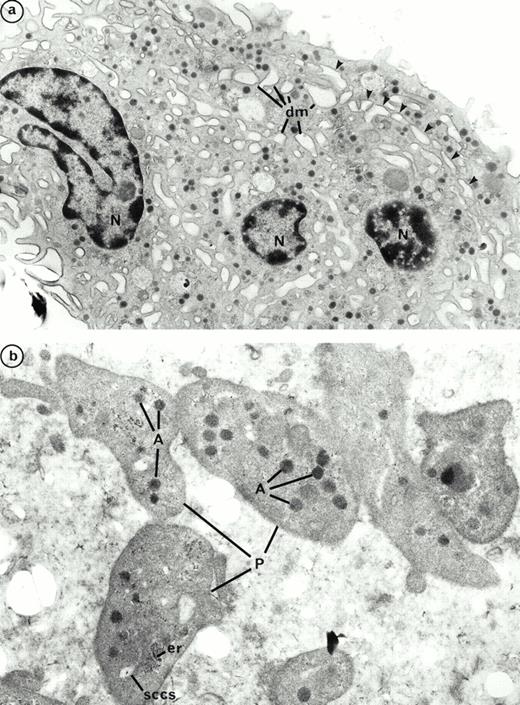

We previously described the ultrastructure of platelet formation by human MKs cultured with PEG-rHuMGDF.29 No substantial differences were observed in the ultrastructure of the platelet-shedding MKs produced in the presence of either PEG-rHuMGDF or the combination of IL-3, SCF, and IL-6. In the two conditions, platelet shedding MKs showed several cytoplasmic expansions which correspond to proplatelets (Figs 9a and10a); constriction zones already individualize distinct platelet fields. In the same way, platelets derived from culture with either PEG-rHuMGDF or the combination of IL-3, IL-6, and SCF were of similar size and exhibited α- and dense granules. Many of these platelets were adherent to MKs; however, they did not exhibit ultrastructural evidence of activation (Figs 9b and 10b). By fluorescent labeling, circumferential microtubule coils and actin filaments were observed with an antitubulin MoAb and phalloidin in the vast majority of the culture-derived platelets (data not shown).

Ultrastructure of platelet shedding MKs and platelets obtained in the presence of the combination of SCF, IL-3, and IL-6 from CD34+ CD41+ cells. (a) A similar mature MK as in Fig 9a with dilatation of demarcation membranes (dm) at the periphery (arrows) (N, nucleus). (b) Platelet-sized-fragments (P) are present with the combination of three cytokines. They are similar to those obtained with PEG-rHuMGDF (Fig 9b). On a proplatelet (PP), a constriction zone area is disposed along the cytoplasmic extension individualizing a distinct platelet field with a vacuole at the level of the future rupture (arrow) (A, α granules; sccs, smooth connected canalicular system; er, endoplasmic reticulum).